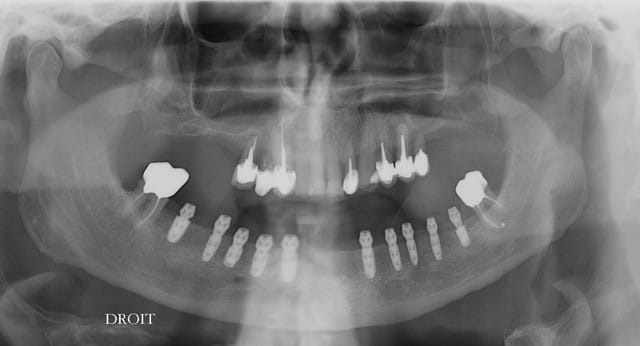

Pourquoi as tu posé des implants de longueurs presque identiques entre les foramens ?

Non,le pano déforme, le diam est diffèrent pour 37, 47 et 45 (4,6 et 4) et 3,4x8 pour le reste sauf 33, 43 x 10mm

La question était sur la longueur des implants entre les foramens mentonnier du N.A.I.

A t'il d'autres foramens plus antérieur voir aussi un foramen incisif?

vu le nombre il ne me semblait pas utile de mettre plus long.